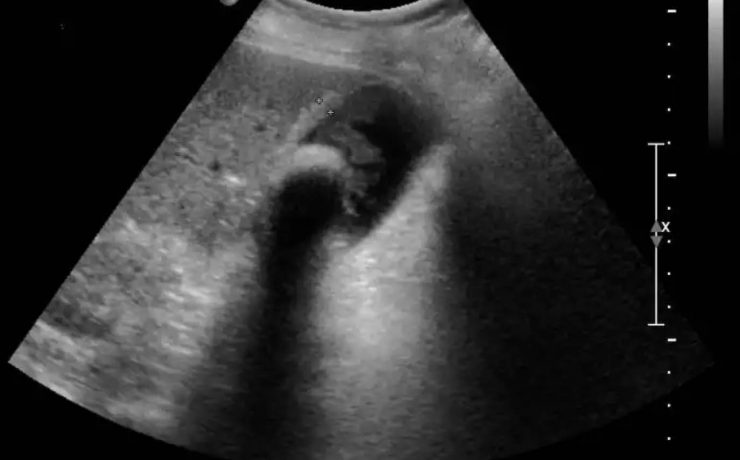

Enfermedad litiásica biliar

Entre un 5 y un 15% de la población occidental presenta litiasis biliar. La mayoría de los cálculos están compuestos por colesterol y se forman en el interior de la vesícula, desde donde pueden migrar a la vía biliar, causando eventualmente cuadros obstructivos. El diagnóstico